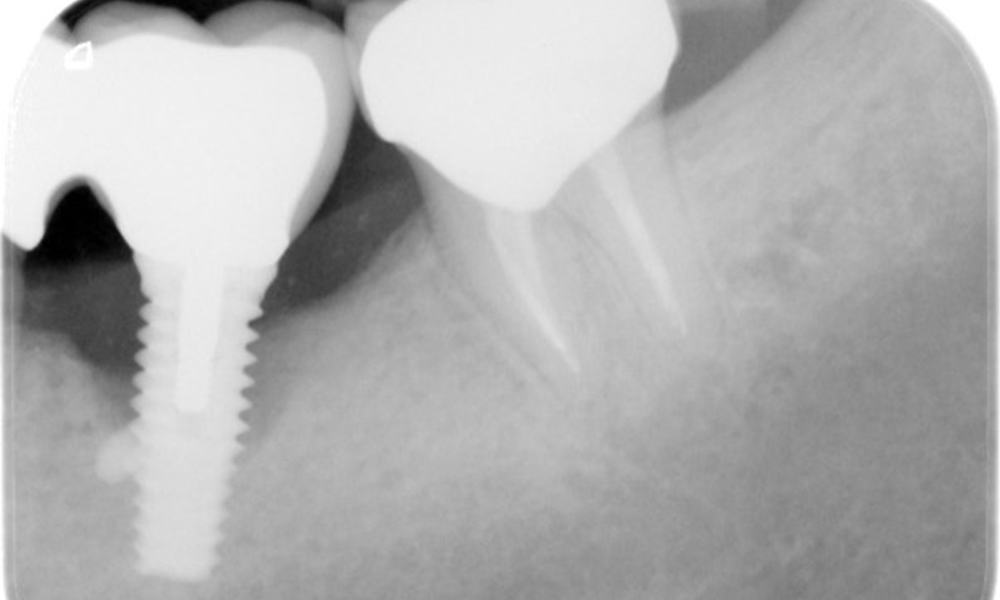

В историята на заболяването на пациента няма особени рискови фактори със специфични дентални последици. Следователно ключовият фактор е изискването по отношение на оралното здраве. В това отношение има данни за дълбочина на сондиране от 5 mm при импланта в 3-ти квадрант, а на рентгеновата снимка - за увеличена костна загуба. Пациентът също така има стабилно понастоящем пародонтално заболяване и две активни начални кариозни лезии.

Рентгеновите снимки показват прогресиращата загуба на костна тъкан в областта на импланта в област 36: рентгенова снимка от 11.02.2021 г. (вляво) и рентгенова снимка от 18.01.2024 г. (вдясно).

ОПГ: 26/02/2024 Дентална рентгенова снимка 18/01/2024